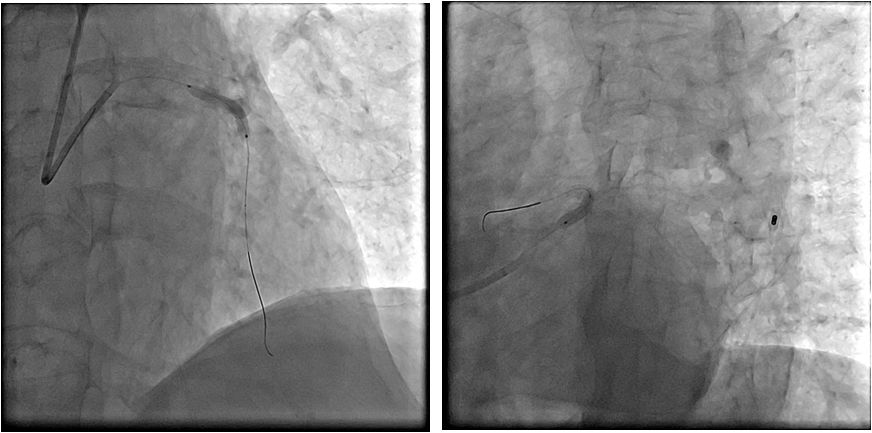

急诊PCI-左冠

急诊PCI--右冠

左冠植入支架

支架植入后

➤ 患者术程比较顺利,胸痛症状明显缓解

➤ 但术中使用多巴胺及IABP辅助下,血压始终在80/50mmHg左右,氧饱和度维持在95-99%